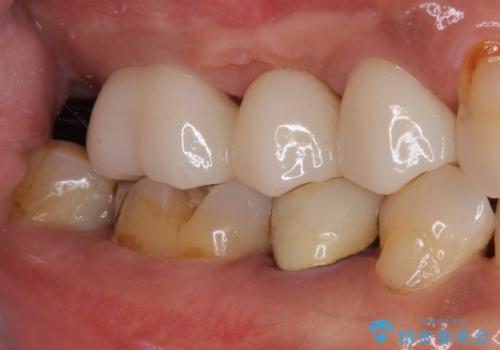

欠けてしまった奥歯 セラミッククラウンによる補綴治療

高強度のジルコニアクラウンとしたことで、強い咬合力でも壊れず、審美性を維持しやすい治療を行うことができました。